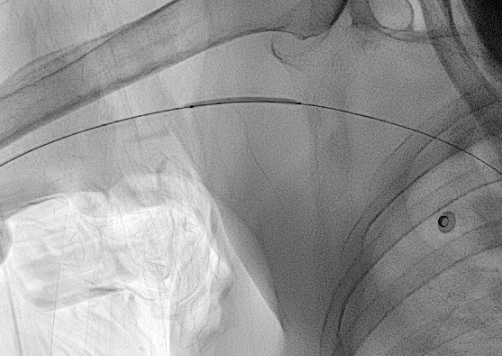

b. 혈관이 막혔거나 아주 좁은 경우

오랜 기간 동안 PICC 를 가지고 계셨거나, 독한 약물 치료를 받으신 분들 중에는 말초 정맥이 막혀버렸거나 아주 좁아져버린 분들이 계십니다. 이 경우 찔렀던 혈관을 그대로 이용하려면 풍선 카테터를 이용하여 혈관성형술을 하거나, 아니면 다른 혈관을 새로 찔러 들어가야 합니다. 두 해결 방법 모두 시간을 늘어지게 하는 방법이지요.